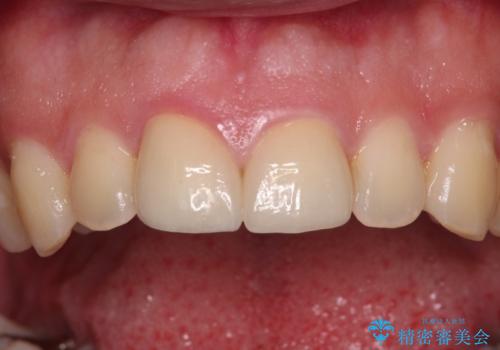

仮歯に置き換え、しみる感覚が改善されてことを確認された後に、オールセラミッククラウンにて補綴治療を行うこととしました。

術後の経過は良好でしたが、レントゲン写真にて神経が失活している時に認められる透過像のようなものが見られました。

神経の反応はあるので失活していないようですが、時間が経過すると衝撃による失活が起こることもあるため、定期的な経過観察が必要です。